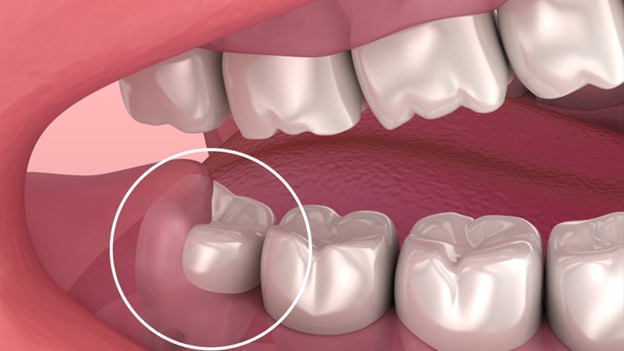

- Răng khôn mọc kẹt

- Cung hàm không đủ khoảng trống, chỉ một phần thân răng mọc lên.

- Thường gây sưng, đau, viêm nướu hoặc lợi trùm.